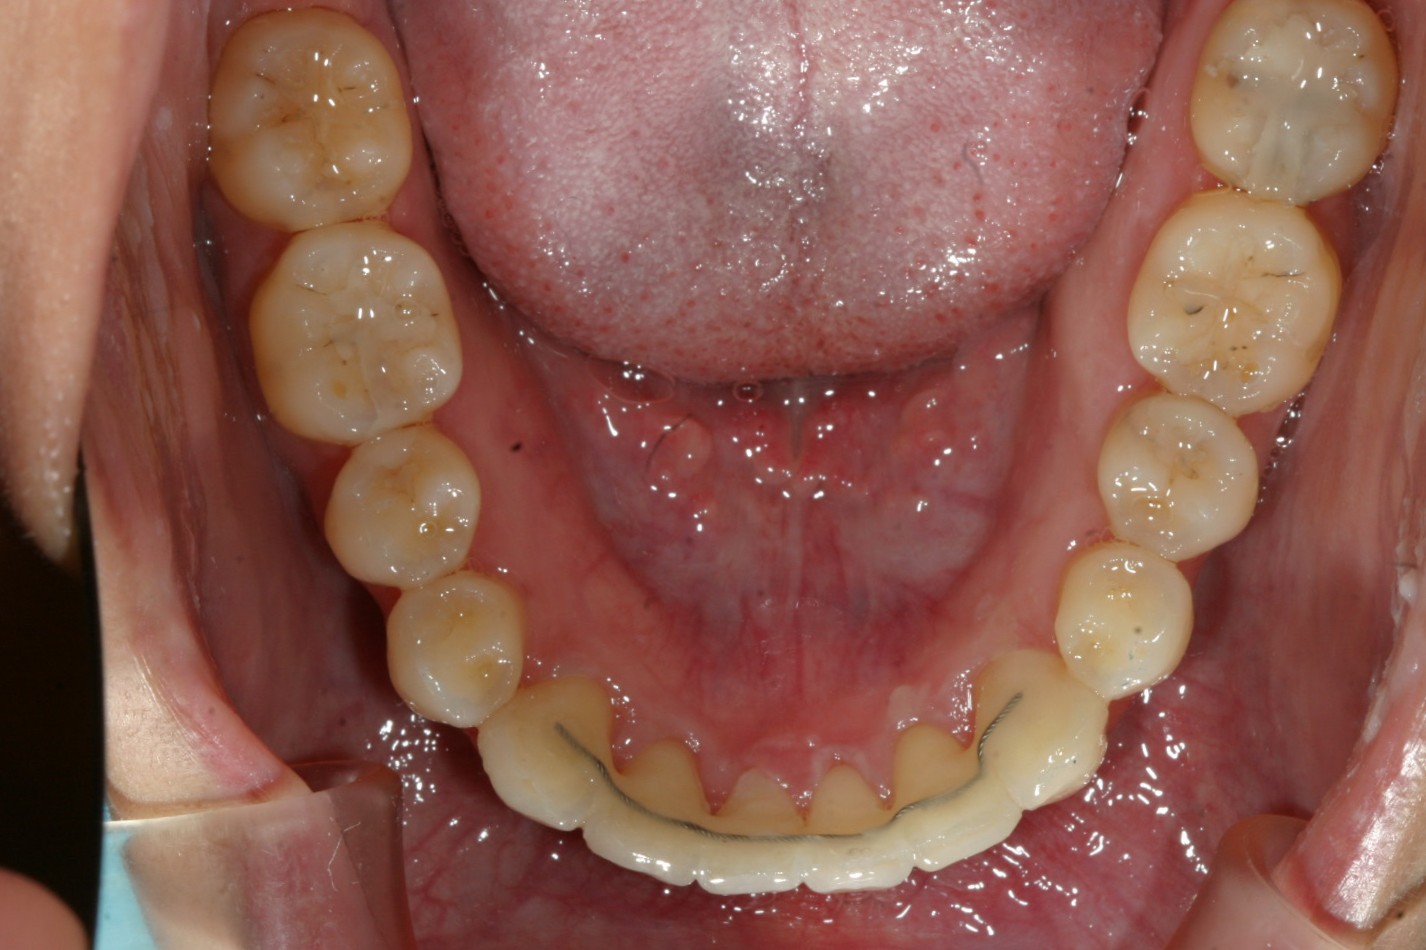

アーチがV字形の為前歯が並ばず前歯が翼状捻転しています。

下顎に少し叢生が見受けられます。

アーチを広げU字型にする事により前歯が綺麗に並びました。

下顎前歯も綺麗に並んでいます。